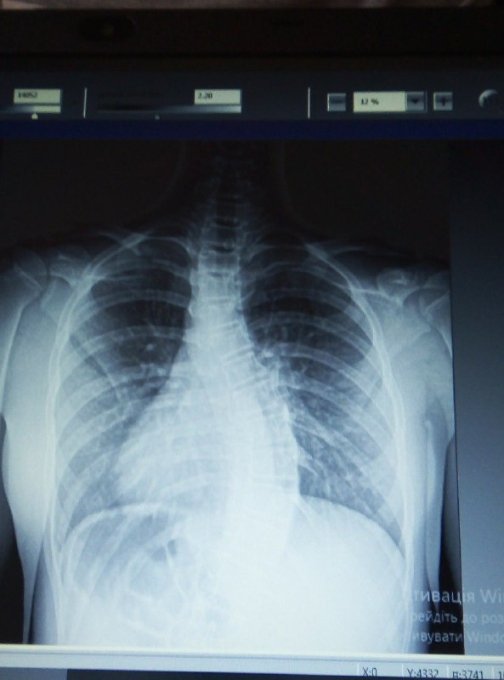

У 13-річної Анастасії Марчак з Володимира-Волинського важкий сколіоз третього ступеня (ідіопатичний грудо-поперековий сколіоз).

Титанова конструкція, яку мають встановити на хребет, допоможе тримати хребці у правильному положенні. Наразі є ризик неминучого викривлення хребта, що дасть ускладнення на роботу внутрішніх органів.